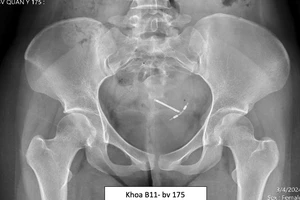

Qua kiểm tra, BS ghi nhận bệnh nhân A bị chấn thương thận trái độ 4, tụ dịch và máu bao quanh thận phải. Bệnh nhân được hồi sức và truyền 500 ml máu, điều trị bảo tồn giữ thận.

Tuy nhiên đến ngày thứ 7, bệnh nhân tiếp tục xuất huyết nên được truyền thêm 500 ml máu và hội chẩn, tiến hành can thiệp mạch máu (bít lỗ rò chảy máu). Hiện tình trạng bệnh nhân đã ổn định và được xuất viện trong ngày 15-4.

Trường hợp bệnh nhân này được BS dùng kỹ thuật can thiệp mạch điều trị chấn thương thận. Đây là ca thứ hai tại BV Nhi đồng 1 áp dụng kỹ thuật này. Ca can thiệp mạch đầu tiên vào một năm trước, qua nhiều lần tái khám, hiện tại tình trạng bệnh nhân đó cũng đã ổn định.